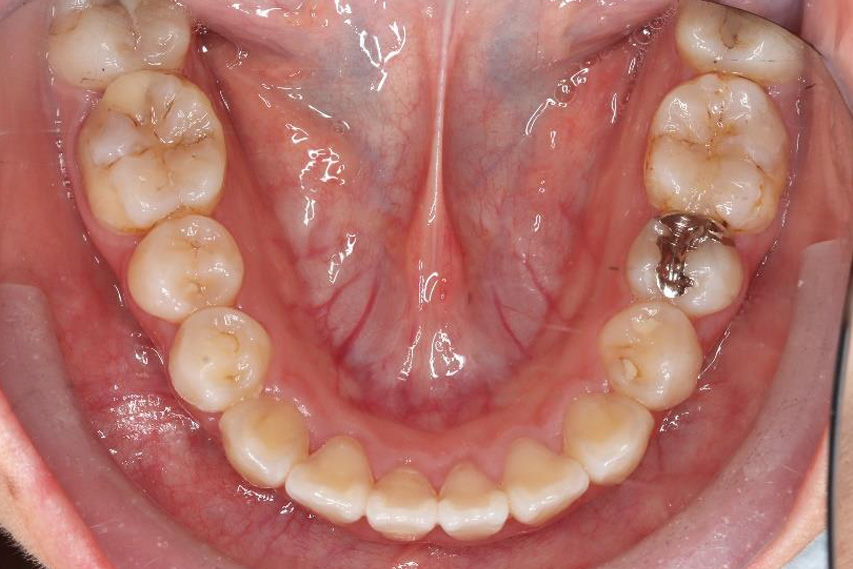

治療前

治療終了前

乱ぐい歯、でこぼこがとても酷い状態になります。歯が前後的に重なってしまっている、八重歯になっているなどがこのジャンルに入ります。

顎の大きさと歯の大きさのギャップが大きく、時には歯を抜かないと矯正治療ができない場合もあります。当院では治療期間が長くなるが抜かない治療方針など、一つの治療プランだけでなく、さまざまな可能性の治療方針を説明させて頂くよう心掛けております。こういった考え方はインフォームド・チョイスと言われ近年大切にされている考え方と言われております。